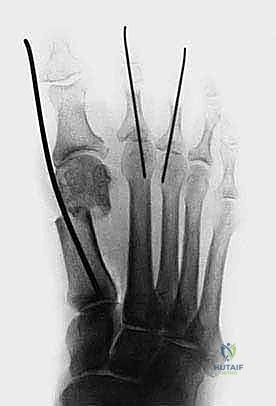

- الأشعة السينية (X-Rays) أثناء تحمل الوزن: هذا هو الفحص الذهبي. يجب أن تُؤخذ صور الأشعة والمريض واقف (يتحمل وزنه على قدميه). من خلال هذه الأشعة، يقوم الدكتور هطيف بقياس الزوايا الهامة بدقة هندسية:

- زاوية إبهام القدم الأروح (HVA): الزاوية بين المشط الأول والسلامية القريبة.

- الزاوية بين الأمشاط (IMA): الزاوية بين المشط الأول والمشط الثاني.

- تقييم موضع العظام السمسمية: لمعرفة مدى خروجها عن مسارها.

- تقييم حالة المفصل: للبحث عن أي علامات لخشونة المفاصل (Arthritis) التي قد تغير من خطة العلاج.

- تثبيت بسيط وفعال: يتم تثبيت العظم بعد قصه باستخدام سلك معدني رفيع جداً (K-wire) يتم إزالته لاحقاً في العيادة بدون ألم، دون الحاجة لترك مسامير دائمة داخل جسم المريض.